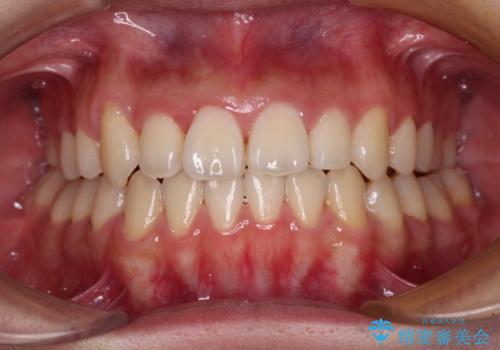

前歯のクロスバイトをインビザライン矯正で改善

- 前歯のデコボコと上下のクロスバイトを気にして来院された患者様です。

インビザラインを用い、IPR(歯と歯の間を削る)と歯列全体を拡大させることで、歯並びを整えていくこととしました。

上の前歯が下の前歯を乗り越える際、奥歯がほとんど咬めない時期があり、乗り越えた後も、インビザライン特有の奥歯の咬みにくさが続きました。

咬み合わせ改善のために治療期間を要しましたが、最終的に奥歯はしっかりと咬めるようになりました。